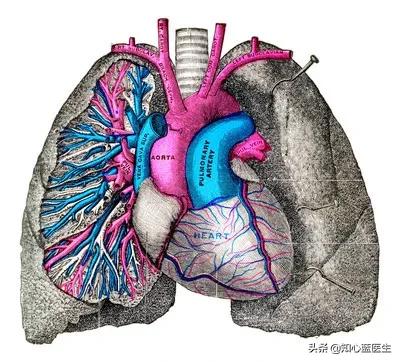

1. le cancer du poumon

(1) Le cancer du poumon est le cancer dont le taux d'incidence est le plus élevé en Chine.Les causes du cancer du poumon ne sont pas particulièrement bien comprises. Les causes du cancer du poumon ne sont pas encore particulièrement claires. Elles comprennent au moins le tabagisme, la pollution de l'air, l'exposition professionnelle, les radiations ionisantes, l'hérédité, les maladies pulmonaires chroniques, le régime alimentaire, etc. En ce qui concerne le cancer du poumon, il est toujours important d'insister encore et encore sur la nécessité d'arrêter de fumer, d'arrêter de fumer, d'arrêter de fumer, pour soi-même et pour sa famille, et le tabagisme passif est également très nocif.

(2) Le symptôme le plus courant du cancer du poumon est une toux sèche irritante ou la présence de sang dans les expectorations.Parfois, les symptômes de la toux ne sont pas si typiques, et il existe de très nombreuses maladies qui provoquent la toux, et même certaines personnes ne présentent aucun symptôme, de sorte que de nombreuses personnes découvrent qu'elles sont déjà à un stade moyen ou avancé du cancer du poumon. L'examen médical le plus courant pour tout le monde dans la vie quotidienne est la radiographie pulmonaire, y compris l'examen médical des employés dans nos hôpitaux. En fait, la radiographie pulmonaire est moins utile pour détecter un cancer du poumon à un stade précoce.Ainsi, pour certaines personnes plus à risque et plus susceptibles de développer un cancer du poumon, il est préférable d'effectuer un scanner thoracique à faible dose afin de pouvoir détecter un cancer du poumon au stade précoce de moins de 1 cm.Nous savons tous que l'examen tomodensitométrique est irradiant et que l'irradiation est l'un des facteurs du cancer du poumon, alors pourquoi continuer à recommander l'examen tomodensitométrique ? Il s'agit ici de la tomodensitométrie thoracique à faible dose, dont la dose de radiation est relativement faible, et qui peut répondre aux exigences du dépistage préliminaire, pour les groupes à haut risque, les avantages l'emportent sur les inconvénients, faire une tomodensitométrie juste pour recevoir une dose relativement faible de radiation, comparé à l'omission de la découverte d'un cancer du poumon à un stade précoce, ce qui est une grande perte ? Pensez-y.

(3) Qui en a besoin ? Les groupes de personnes suivants présentent un risque élevé. Âge supérieur à 40 ans, tabagisme depuis plus de 20 ans ; antécédents familiaux de tumeurs malignes ; exposition prolongée au tabagisme passif ; patients atteints de broncho-pneumopathie chronique obstructive (BPCO) ou de fibrose pulmonaire ; personnes ayant été exposées à des fumées de cuisine pendant une longue période ; expositions professionnelles, exposition à l'amiante, à l'uranium et à d'autres substances.